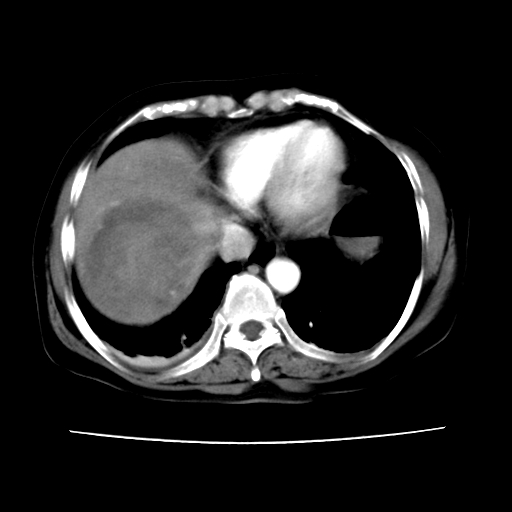

2008-11-10ct平扫(其间去中山医院诊治未行特殊治疗)

2008-11-10ct平扫见并肝内、血膜下血肿基本吸收,肝内低密度灶缩小。此时再做增强ct应有显着意义。对患者/医者都好!

从平扫+增强及治疗后复查片,病变明显缩小,不考虑肝癌出血可能,还是考虑为良性病变可能性大;单纯血肿并包膜下积液吧,病变强化没法解释,肝血管破裂出血吧,增强不符合典型血管瘤的表现,良性肿瘤破裂出血吧,复查片看来好像也不太支持(没做强化也不太好说)。本人还是考虑单纯肝内血肿并包膜下积液,强化是不是血管有外渗。

患者自6月至11月,如果是肝癌,没有经过特殊治疗,想必应该会有所进展吧,而不是ct所见,反而似有病灶减小的趋势。建议增强。

同意肝内肿块破裂致腹部疼痛,但不考虑肿瘤及血管瘤,增强不是血管瘤的特点,肿瘤半年时间内未经特殊治疗竟然快消失?考虑炎性改变或脓肿或寄生虫